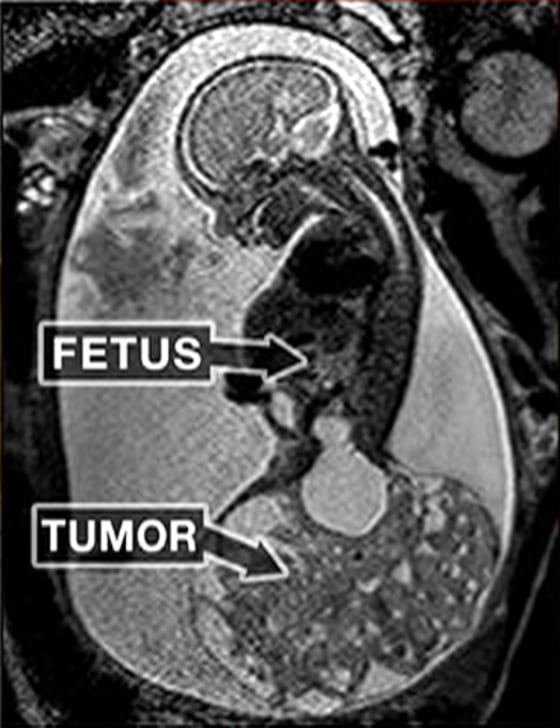

The ultrasound imaging showed what appeared to be a balloon growing out of Macie’s tailbone, but it was filled with blood vessels and was the same size as the fetus. The growth wasn’t malignant, yet it was nonetheless fatal.

“This tumor was enormous,” Cass explained. “It was the size of a grapefruit,” says the narrator.

“This is a once-in-a-lifetime opportunity.” “It’s probably one out of every 40,000 babies,” Cass explained. “These tumors can grow and stay small for a long period, and they don’t have a big impact on the fetus.” This tumor developed extraordinarily quickly in Macie’s case… and it was practically robbing her body of the blood it required to flourish. If nothing had been done, she would have perished.”

When doctors discovered one, they relaxed the womb and retrieved around 80% of Macie Hope’s body, which weighed less than a quarter of a pound, leaving only the head and upper body in the womb. Due to the risk of the fetus going into cardiac arrest if she was exposed to the air, the doctors worked rapidly to remove the tumor and return Macie to the safety of the womb.